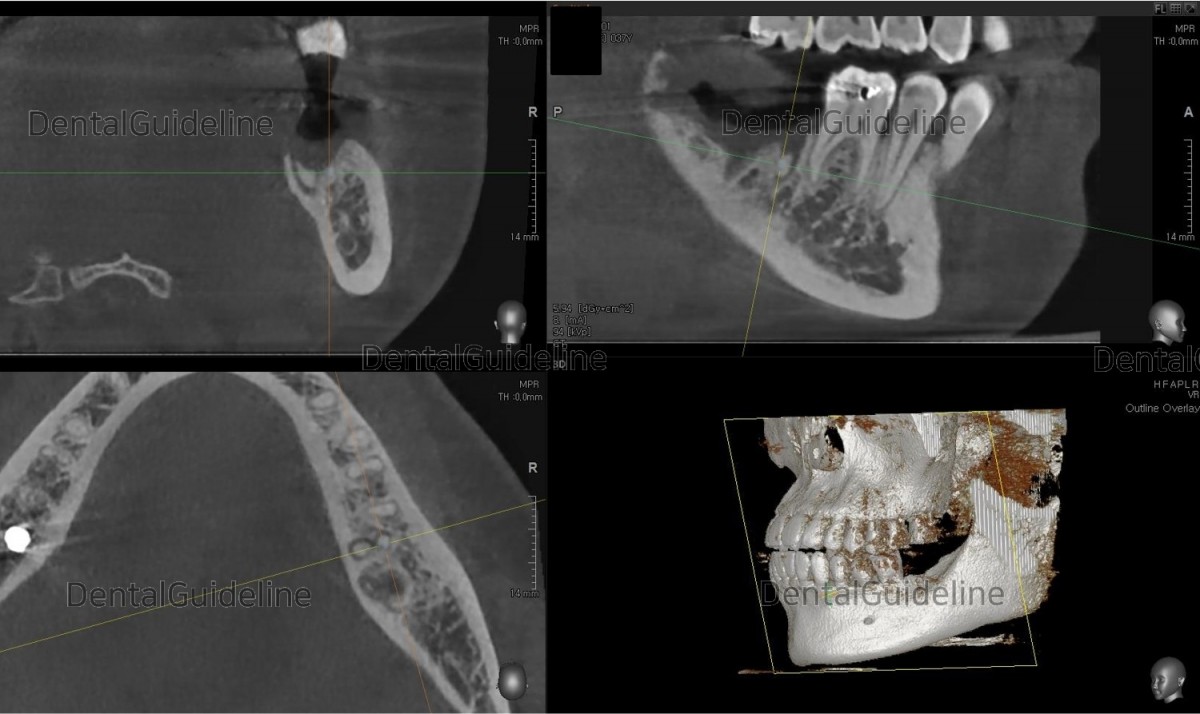

3. CBCT shows the root rest.

8. CBCT scan image.